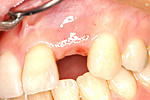

① 右上34番の歯がありません。

② インプラントで2本分の歯を作りました。

20才代 男性

総額:45万円(税別)

治療期間:3ヵ月

リスク副作用:骨の吸収による審美性の低下。ブラッシング不良によるインプラント周囲炎の発生。